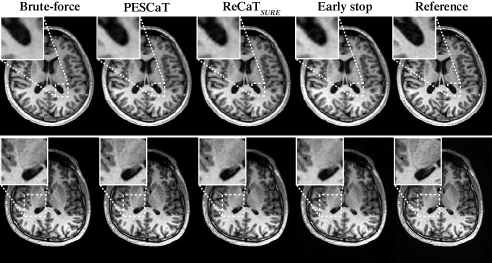

Next, PESCaT was demonstrated for in vivo bSSFP, T1-weighted, and ToF imaging of the brain. Representative reconstructions with R=6 for bSSFP and R=4 for T1-weighted and ToF acquisitions are displayed in Figs. 4, 5, and 6. Representative reconstructions of individual phase cycles in the bSSFP dataset, and of cross-sections in the ToF dataset are shown in Supp. Fig. 11. Overall, PESCaT and ReCaTSURE reconstructions perform similar to the brute-force optimized reconstructions. Yet, PESCaT yields slightly lower levels of residual aliasing in comparison to ReCaTSURE, and this difference is particularly noticeable for visualization of small vessels in ToF images (Fig. 6). The improvement in reconstruction quality with PESCaT is more prominent when ReCaTSURE is stopped early to match its reconstruction time to PESCaT.

Quantitative assessments of the in vivo reconstructions are listed in Tables II, III, and IV. For all datasets and R, PESCaT yields the closest performance to the brute-force reconstruction among alternative self-tuning methods. For bSSFP datasets, PESCaT improves PSNR by dB over ReCaTSURE and by dB over ReCaTSURE with early stop (meanstd. across three subjects, average of R=2, 4, 6). For T1-weighted datasets, PESCaT improves PSNR by dB over ReCaTSURE and by dB over ReCaTSURE with early stop (meanstd. across three subjects, average of R=2, 4). For ToF datasets, PESCaT improves PSNR by dB over ReCaTSURE and by dB over ReCaTSURE with early stop (meanstd. across three subjects, average of R=2, 4). Compared to empirically-tuned ReCaTfixed, PESCaT improves PSNR by dB for bSSFP datasets, by dB for T1-weighted datasets, and by dB for ToF datasets (meanstd. across three subjects, average of R=2, 4, 6 for bSSFP, average of R=2, 4 for T1-weighted and ToF datasets. Because both methods were allowed to optimize parameters in training subjects, these results suggest that selecting different regularization parameters for each coil/acquisition/subband/level improves reconstruction performance. Compared to PESSPIRiT, PESCaT improves PSNR by dB for bSSFP datasets, by dB for T1-weighted datasets, and by dB for ToF datasets (meanstd. across three subjects, average of R=2, 4, 6 for bSSFP, average of R=2, 4 for T1-weighted and ToF datasets). Performance enhancement is even more prominent compared to PESSPIRiT variants that only include sparsity or TV regularization.